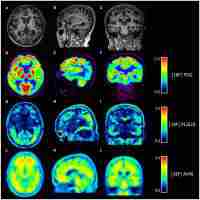

| Abstract | Background Glucocerebrosidase (GBA) heterozygous variants are the most important genetic risk factor for the development of alpha-synucleinopathies (i.e., Parkinson’s disease and Dementia with Lewy Bodies). Herein, we report for the first time on a patient with a clinical diagnosis of Posterior Cortical Atrophy, carrier of the common GBA heterozygous variant N370S (c.1226A > G). Case presentation A 44-year-old woman with positive familial history for Dementia with Lewy Bodies disclosed three related signs characterizing the Balint’s syndrome: ocular apraxia, optic ataxia and simultanagnosia. Over 2-year follow up, overt gaze apraxia (psychic paralysis of gaze) appeared leading to functional blindness. Given her young age at onset and positive familial history, she underwent a next-generation-sequencing (NGS) based screening of a panel of 32 genes related to neurodegenerative conditions within the ANAMNESYS (An origiNal Approach to study faMiliarity in NEurodegenerative SYndromeS) study. NGS demonstrated the N370S variant in the GBA gene (rs76763715), confirmed by Sanger sequencing. This is a relatively common variant, with predicted mild impact, already reported to occur in 2.4% of PD Italian patients; however, neither this nor other GBA variants have ever been reported to date in patients with Posterior Cortical Atrophy. Glucocerebrosidase activity was investigated and found to be significantly reduced (4.72 nmol/h/mg) compared to healthy controls as well as patients affected by neurodegenerative diseases, further supporting pathogenicity of the GBA variant. Conclusions We report on a patient with a clinical diagnosis of Posterior Cortical Atrophy, carrier of the GBA heterozygous variant N370S (c.1226A > G; p.Asn409Ser) determining reduced GCase activity. This report also confirms the role of NGS-based targeted gene analysis in detecting peculiar clinical phenotypes associated with known pathogenic mutations and reinforces the knowledge that carriers of genetic variants often present phenotypic overlaps across different neurodegenerative syndromes, highlighting the limitations of current clinical diagnostic criteria in defining boundaries between distinct conditions and the difficulties of clinicians in reaching the best clinical diagnosis. |